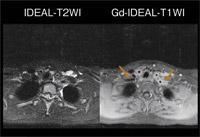

図3は、高安病(大動脈炎症候群)を疑う症例のIDEALによる脂肪抑制T2強調像とT1強調像であるが、ともに動脈壁と周囲の異常信号/増強効果が認められ、血管壁に沿った炎症が非常によくわかる。IDEALは、造影後のT1強調像でも均一な脂肪抑制効果を可能にする理想的な撮像法と言える。

図3

図3 IDEAL(高安病を疑う症例)